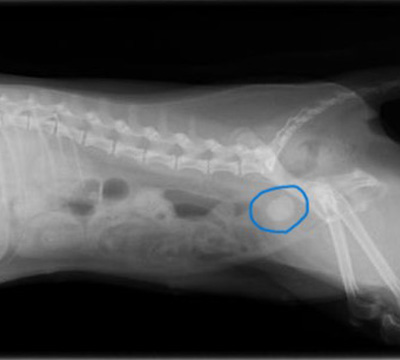

- 膀胱結石レントゲン

- 摘出した膀胱結石